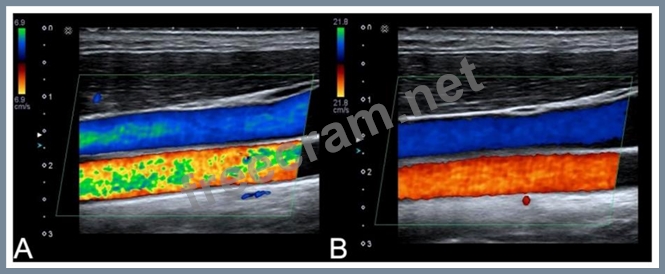

Which adjustment resulted in the change from image A to image B?

Question 5: Which adjustment resulted in the change from image A to imag...